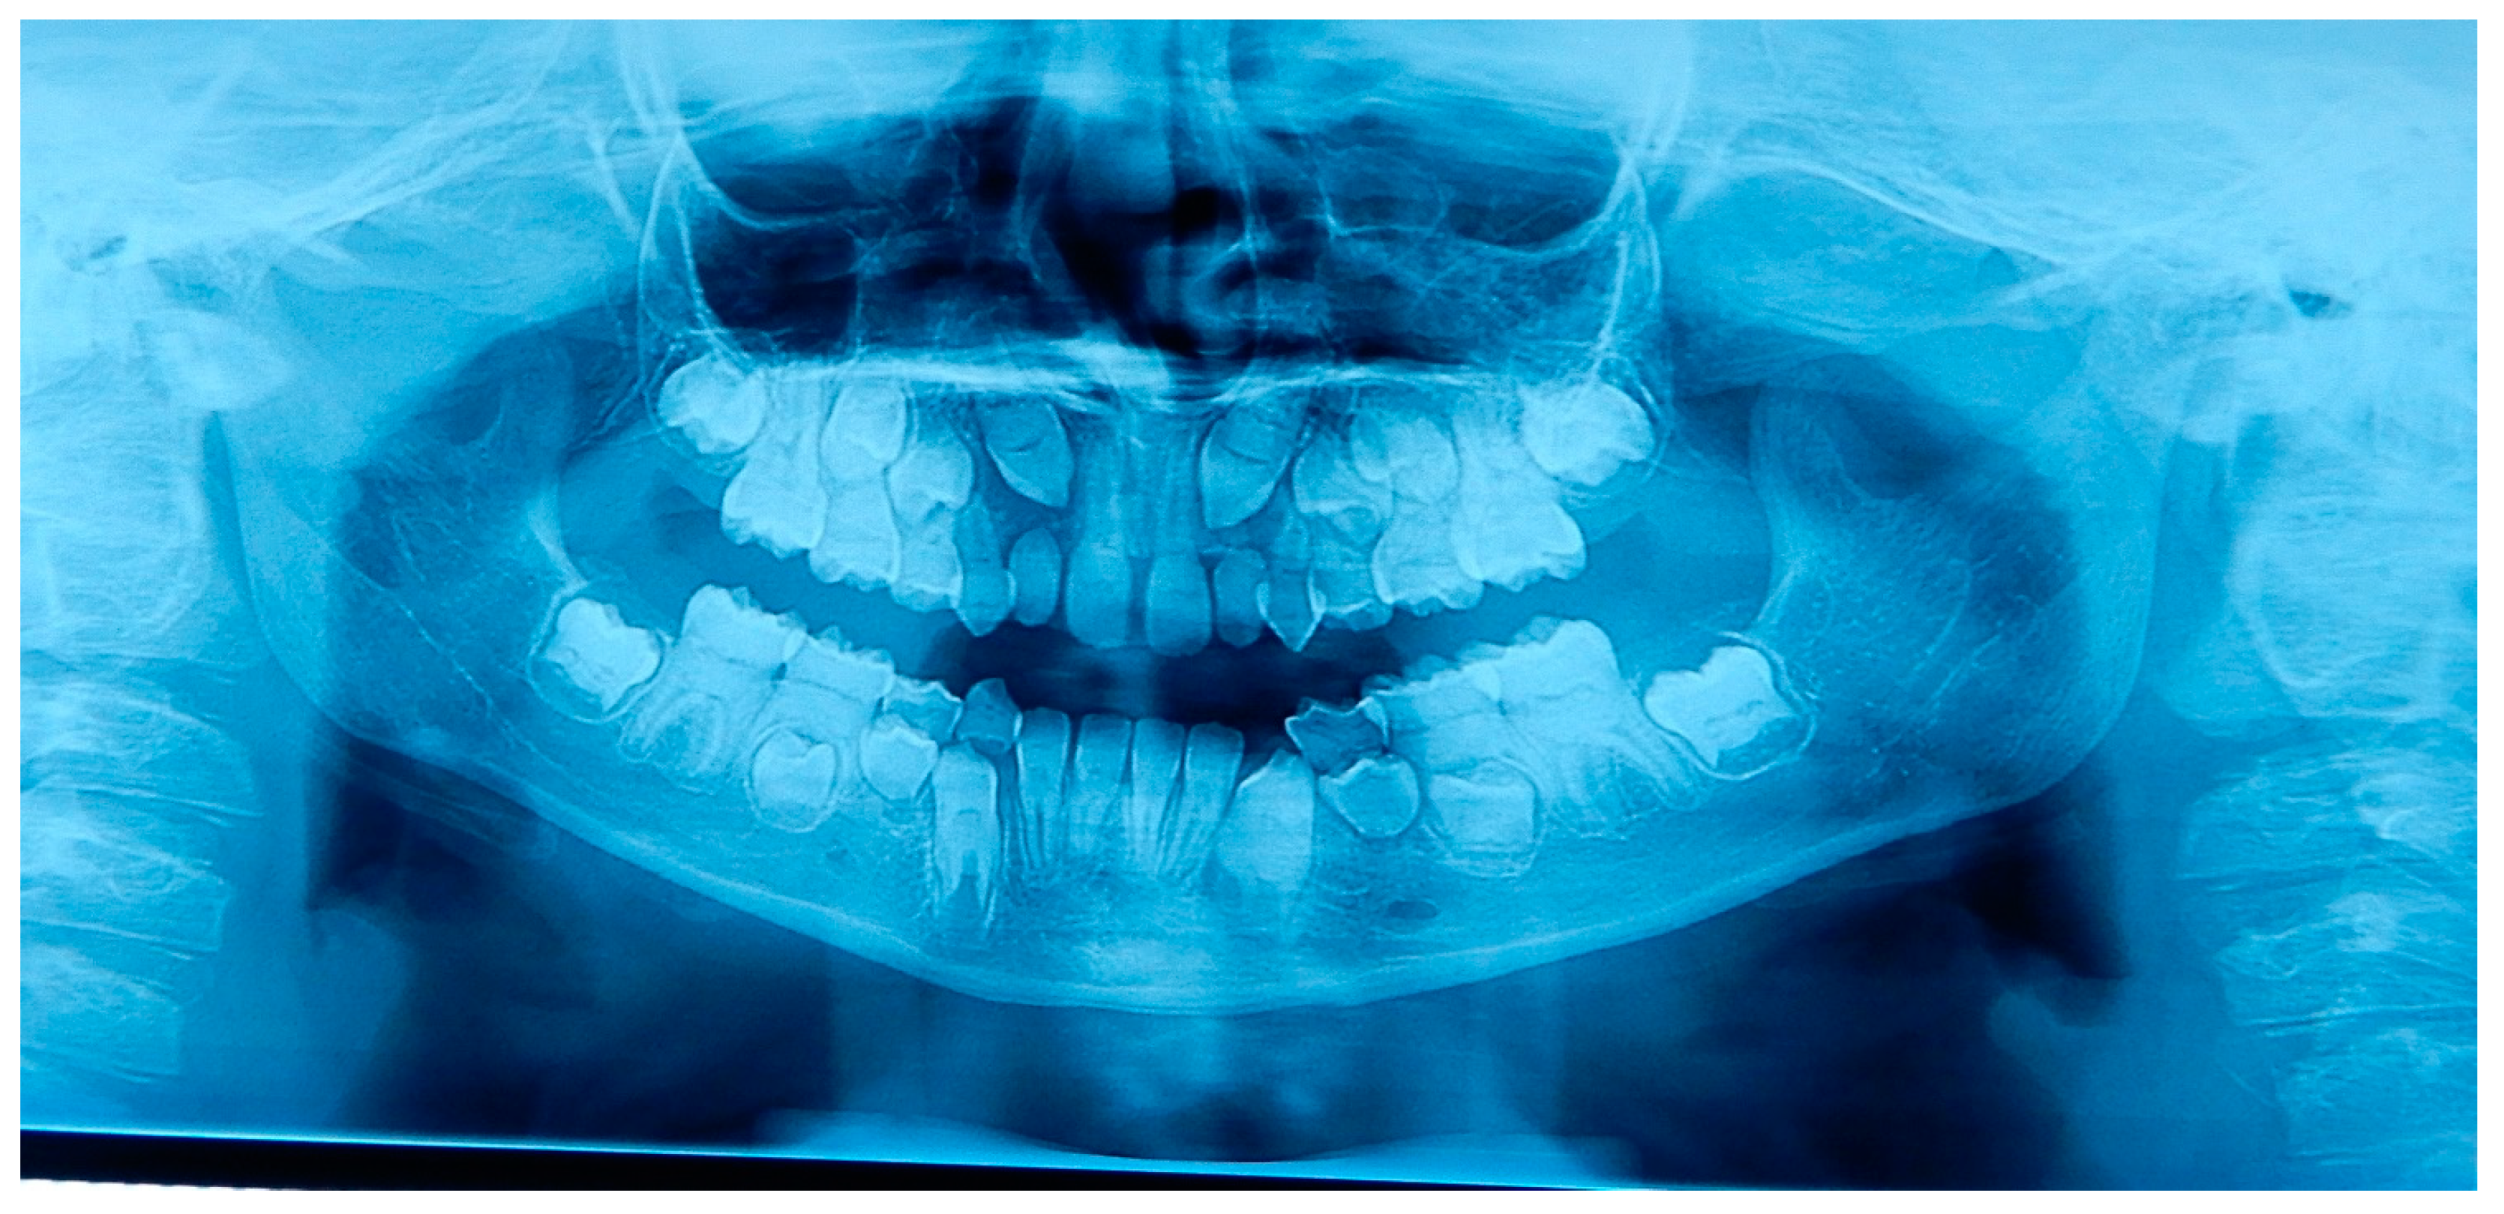

2.1. Patient A